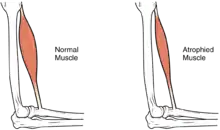

In the long term, the loss of muscle function can have additional effects from disuse, including atrophy of the muscle. Immobility can lead to pressure sores, particularly in bony areas, requiring precautions such as extra cushioning and turning in bed every two hours (in the acute setting) to relieve pressure.[51] In the long term, people in wheelchairs must shift periodically to relieve pressure.[52] Another complication is pain, including nociceptive pain (indication of potential or actual tissue damage) and neuropathic pain, when nerves affected by damage convey erroneous pain signals in the absence of noxious stimuli.[53] Spasticity, the uncontrollable tensing of muscles below the level of injury, occurs in 65–78% of chronic SCI.[54] It results from lack of input from the brain that quells muscle responses to stretch reflexes.[55] It can be treated with drugs and physical therapy.[55] Spasticity increases the risk of contractures (shortening of muscles, tendons, or ligaments that result from lack of use of a limb); this problem can be prevented by moving the limb through its full range of motion multiple times a day.[56] Another problem lack of mobility can cause is loss of bone density and changes in bone structure.[57][58] Loss of bone density (bone demineralization), thought to be due to lack of input from weakened or paralysed muscles, can increase the risk of fractures.[59] Conversely, a poorly understood phenomenon is the overgrowth of bone tissue in soft tissue areas, called heterotopic ossification.[60] It occurs below the level of injury, possibly as a result of inflammation, and happens to a clinically significant extent in 27% of people.[60]

Muscle mass is reduced as muscles atrophy with disuse.